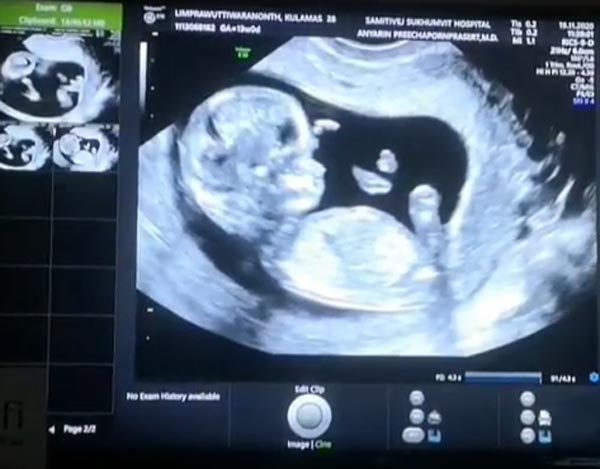

โดย ขนมจีน กุลมาศ ออกมาประกาศข่าวดีผ่านทางอินสตาแกรมเป็นภาพถ่ายคู่กับคุณสามีและถือภาพอัลตราซาวด์ลูกน้อยในท้องให้ได้ชมกันเป็นครั้งแรก พร้อมเผยว่าขณะนี้อายุครรภ์ 13 สัปดาห์แล้ว และยังบอกด้วยว่าครอบครัวตื่นเต้นกันสุด ๆ ซึ่งช่วงก่อนหน้านี้ว่าที่คุณแม่ก็เกิดอาการแพ้ท้องหนักมาก จนต้องงดรับงานหลาย ๆ งานไป แต่ขณะนี้โอเคขึ้นมากแล้ว

นอกจากนี้ ขนมจีน ยังได้เผยคลิปอัลตราซาวด์ลูกน้อยในท้อง พร้อมพูดถึงเรื่องของ จมูก ที่พุ่งโด่งมาแต่ไกล และแซวว่า ไม่ต้องพาไปเกาหลีแล้ว "ว่าด้วยเรื่องจมูกลูกกกก คุณคะ อิชั้นดีใจลูกได้จมูกพ่อค่ะ แม่ไม่ต้องพาลูกไปเกาหลีแล้ววววว ป.ล. สามีทักท้วงเรื่องนามสกุลในประวัติมาก ทำไมนามสกุลเดิม เปลี่ยนให้ด้วยนะครับ ใจเย็นค่ะคุณพ่อ #knomjeankenbaby #knomjeankenlovestory"